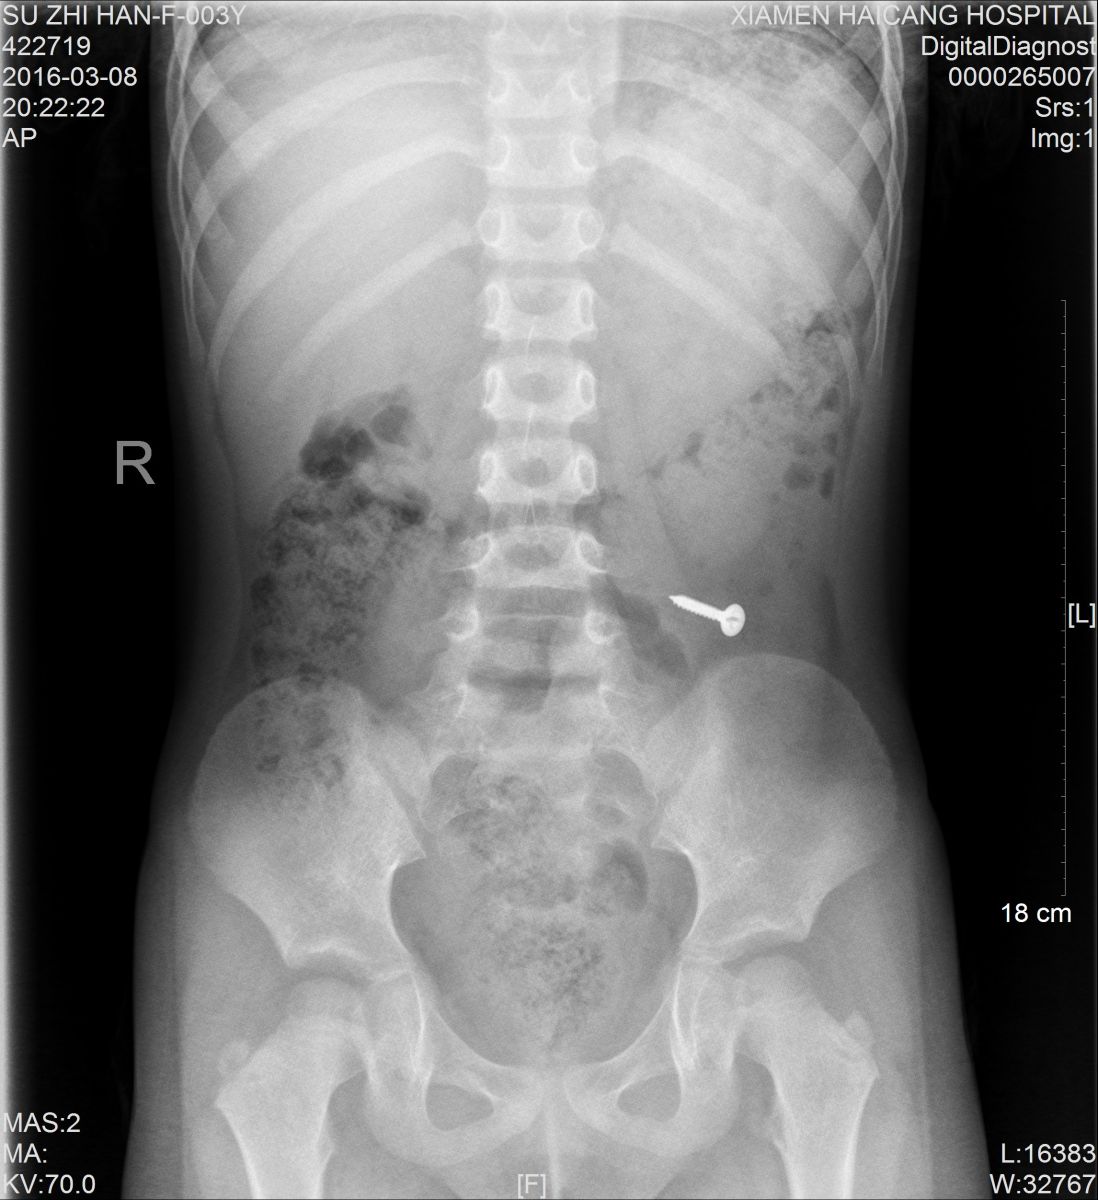

值班的医生了解情况后,马上安排小桐做X光片检查,检查影像一出来,大家都吓了一跳,只见小桐身体里清晰地躺着一个金属异物,经与小桐再三辨认,确定是一颗螺丝钉。确诊后,医生马上安排小桐转诊小儿外科治疗。

据医生介绍,由于患者年龄太小,手术损伤大,目前没有腹痛、腹膜炎等肠穿孔征象,螺丝钉不是很大,有可能自行排出,便建议随访,让患儿多吃些富含纤维素的食物,如韭菜、芹菜,以促进消化道蠕动,加速螺丝钉的排出。同时告知小桐父母需密切观察大便中是否有钉子排出,如有呕血、腹痛、发烧等异常情况,需马上就医。

3天后,小桐再来医院拍片复查,发现螺丝钉已经顺利排出,这才让父母放心。